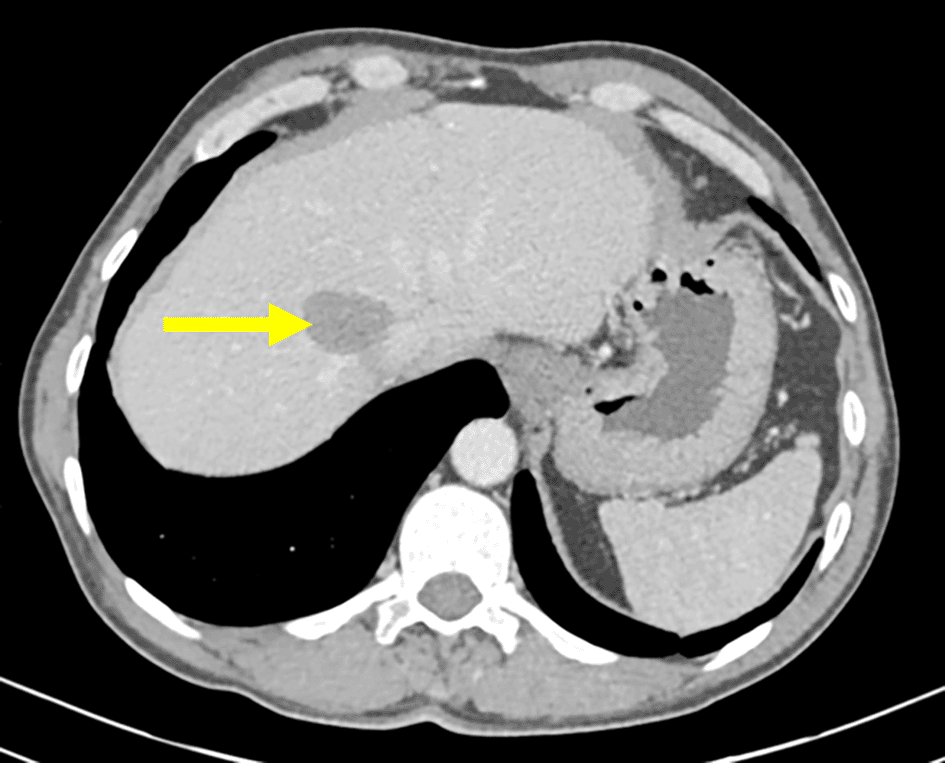

The patient was followed up at the department of abdominal surgery, a multiple organ hydatidosis including 13 hydatid cysts were discovered: the lungs, the liver ( Figure 1), the left heart ventricle, the left kidney (Figure 2), the abdomen cavity, the muscles (psoas, adductors), and the subcutaneous gluteal area. In fact, the patient has been experiencing at the beginning a bronchial syndrome symptom, including coughing, and hemoptysis. The laboratory tests were performed and were within the normal range except for high hydatid serology. A Chest CT scan showed three lungs’ cysts. With the exception of the psoas cyst, which is associated with a lower limb paresthesia, the remaining cyst locations identified above were discovered during the preoperative search for additional cysts sites.

Renal involvement is also rare (2–3%) and it is usually associated with disseminated disease, they are most commonly asymptomatic, as reported in the present case. The diagnosis was made by an abdominal CT scan which has a sensitivity of 98% in diagnosing hydatid disease.8